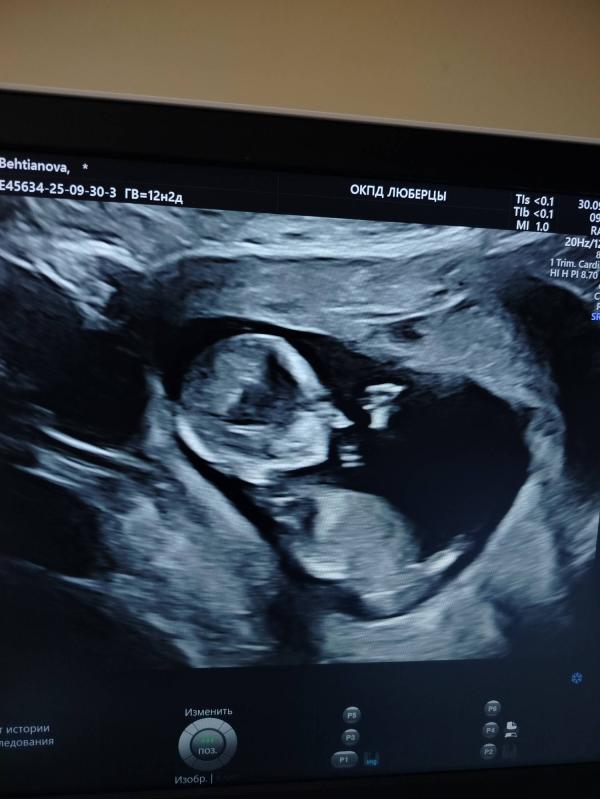

Сегодня был 1 скрининг, 12.2 недели. Очень волновалась, славу Богу все хорошо🥹

Фотку распечатать не удалось, зато дали сфотографировать, даже в 3D формате😍

Тут увидела многие кидают фото с узи и гадают по строению головы какой будет пол🤣 Кого видите ? 😁

Похоже на девочку, но не факт конечно 🙈